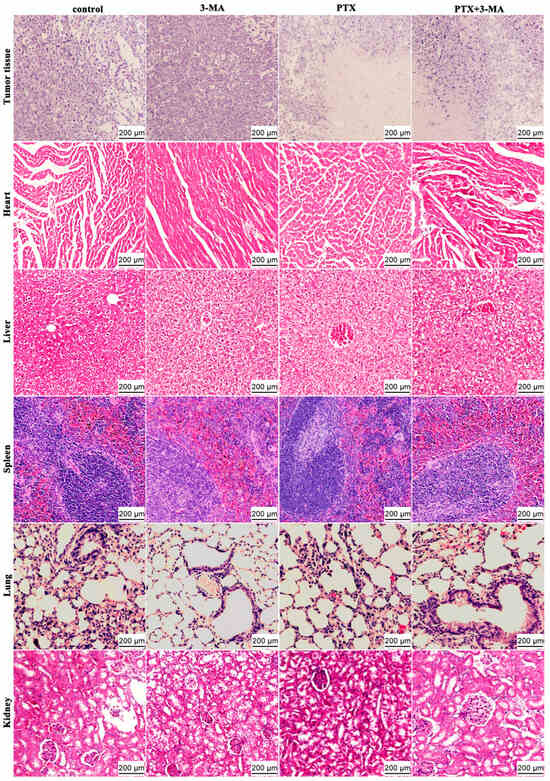

2.3. HE Staining of Tumor and Organ Tissues in MDA-MB-231 Tumor-Bearing Nude Mice After Combined Treatment of PTX and 3-MA

4.5. Histopathological Analysis